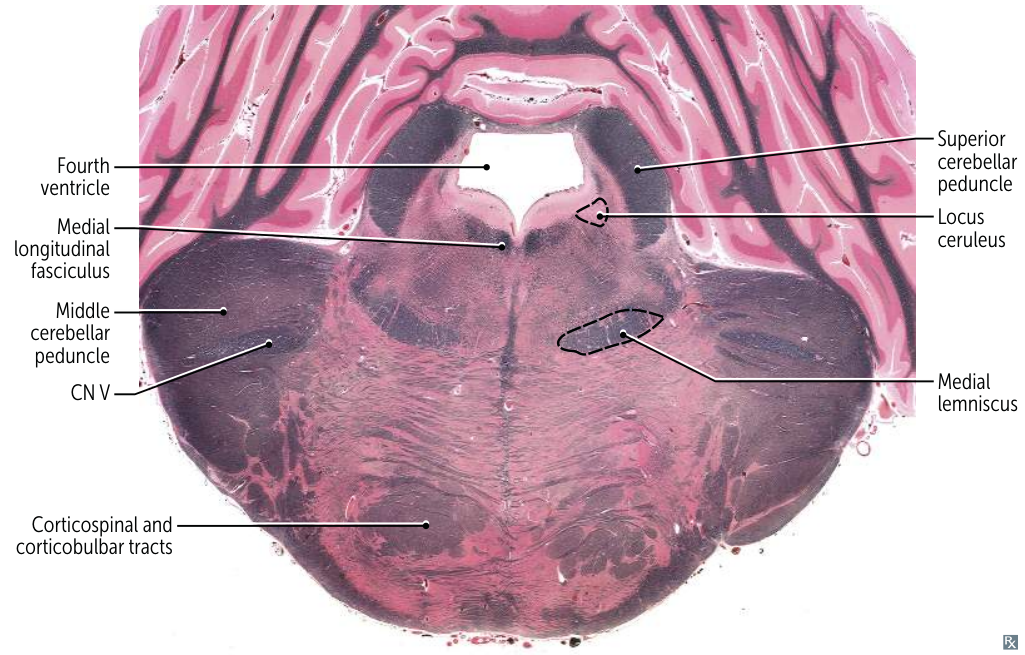

Rostral Pons:

- Most Distinctive Feature: Massive Middle Cerebellar Peduncles forming the wide, bulbous sides of the pons. Trigeminal (CN V) nuclei and nerve are present.

- CN V (Trigeminal) nuclei:

- Main Sensory Nucleus: Processes discriminative touch and pressure sensations from the face.

- Motor Nucleus: Controls muscles of mastication (chewing).

- (The Spinal Trigeminal Nucleus begins here and extends down; the Mesencephalic Nucleus extends up).

- CN VI (Abducens) nucleus: Controls the lateral rectus muscle of the eye (abduction).

- CN VII (Facial) nucleus: Controls muscles of facial expression, taste from the anterior two-thirds of the tongue, and stimulates salivary and lacrimal glands.

- CN VIII (Vestibulocochlear) nuclei (partly): The Cochlear and Vestibular nuclei are located primarily at the junction between the pons and medulla (pontomedullary junction).